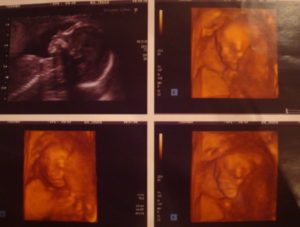

УЗИ на 17 неделе беременности уже может показать пол ребенка, если он повернется к датчику тем самым местом. Однако врача будут волновать другие показатели: размеры малыша и матки и их соответствие сроку, сердцебиение плода, его двигательная активность, состояние маточного миометрия, околоплодных вод, отсутствие грубых аномальных нарушений и так далее.

- Второе плановое УЗИ (показывает развитие ребенка в утробе матери) или повторный скрининг;

Обследование состоит из двух частей – УЗИ и проведения биохимических анализов крови.

При проведении УЗИ на 17 неделе беременности проводится:

- фетометрия (определение размеров плода);

- диагностика развития внутренних органов;

- оценка развития структуры лица;

- количество околоплодных вод;

- кроме того, специалист проверит, в каком состоянии находится плацента.

При проведении второго скрининга беременности не обязательно нужно сдавать кровь. Если проведенное на 17 неделе беременности УЗИ дало хорошие результаты, на биохимические анализы направлять будущую маму не обязательно. Но в некоторых случаях назначается тройной тест, во время которого проводится определение содержания в крови: